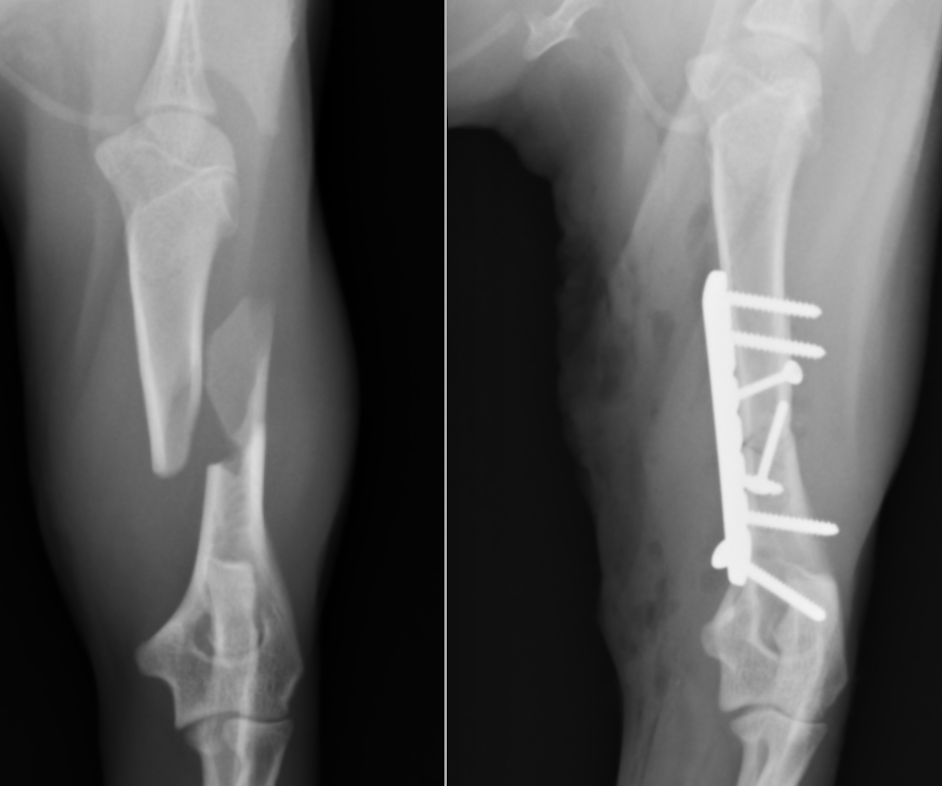

上腕骨粉砕骨折した猫

犬猫では上腕骨の骨折は比較的稀な疾患です。猫の上腕骨は捻りの力が強く発生するのと外固定が困難であるため第Ⅰ選択の治療がプレートスクリュー固定となります。固定強度が弱い場合には髄内ピンをプラスすることもあります。

今回の症例は5ヶ月の上腕骨粉砕骨折です。粉砕している場合骨片をうまく合わせることができれば固定強度が強くなります。粉砕している骨が小さすぎたり、合わせることが困難な場合には固定強度が著しく低下するため髄内ピンなどを追加します。

この症例の場合粉砕骨片をラグスクリュー法という方法である程度合わせることができたのですが、一部欠損が合ったためロッキングプレートという強度の高いプレートを使用しました。

術後の経過は順調で癒合した段階でプレート抜去を行い、問題なく経過しています。